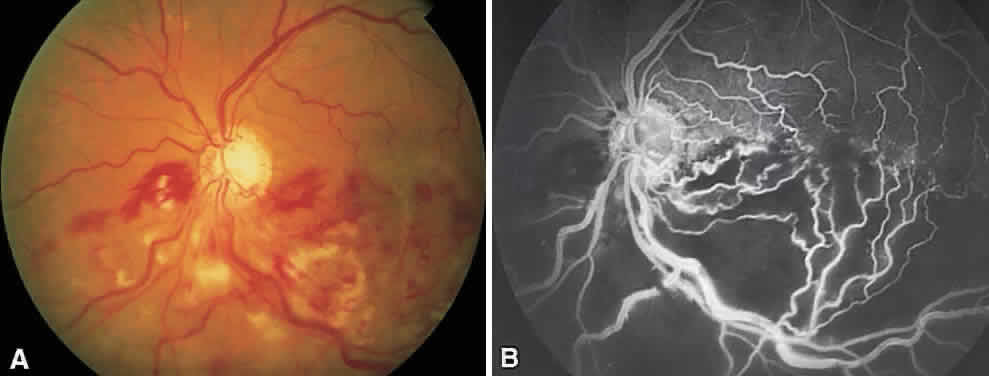

Branch retinal vein occlusions (BRVOs) usually occur at arteriovenous crossings, with the arteriole typically crossing anterior to the vein.44 Visual loss may be a result of macular hemorrhage or edema, capillary nonperfusion, RPE changes or vitreous hemorrhage (Fig. 4). The Branch Vein Occlusion Study (BVOS) was a prospective, randomized multicenter clinical trial designed to address the following questions: Is macular argon laser photocoagulation beneficial in preserving or improving central visual acuity in eyes with 20/40 or worse vision secondary to macular edema related to a branch vein occlusion? Can peripheral scatter argon laser photocoagulation prevent the development of retinal neovascularization? Can peripheral scatter laser treatment prevent vitreous hemorrhage from retinal neovascularization? This study demonstrated conclusively the effectiveness of argon laser photocoagulation for the treatment of macular edema and retinal neovascularization (Fig. 5).45,46 After 3 years of follow-up, the gain of at least two lines of visual acuity from baseline maintained for two consecutive visits was significantly greater in treated eyes. As a result, laser photocoagulation is now recommended for patients with macular edema from branch vein occlusion. In addition, Roseman and Olk have shown that krypton red is effective for treating macular edema and neovascularization from BRVO in eyes with cataracts, vitreous hemorrhage, or extensive intraretinal hemorrhage.47 Visual improvement, however, is unlikely in cases with marked capillary nonperfusion and severe visual loss.

Fig. 4. A. Hemiretinal vein occlusion. B. Fluorescein angiogram reveals severe capillary nonperfusion.

Fig. 5. A. Fluorescein angiogram of a superotemporal branch retinal vein occlusion with marked retinal ischemia. The localized hyperfluorescence in the papillomacular bundle represents retinal neovascularization. B. Three years after sector laser photocoagulation to area of retinal nonperfusion.

If, after 3 months, visual acuity is 20/40 or worse, laser treatment is indicated. Grid treatment with a spot size of 100 to 200 μm and 0.1-second duration is placed in areas of leakage as shown on FA. There should be sufficient clearing of retinal hemorrhage before FA or laser because visual acuity may increase and FA may be more useful in terms of evaluating the macula for evidence of capillary nonperfusion. Recommendations concerning intensity of burns, spacing between laser burns, and treating near the fovea as well as potential complications are similar to those for laser treatment of DME. Eyes are reevaluated in 4 months and retreated if persistent macular edema accounts for the decrease in visual acuity.

The BVOS also assessed the role of scatter photocoagulation in preventing formation of retinal neovascularization and subsequent vitreous hemorrhage in patients with ischemic occlusions.47 It was noted that scatter argon laser photocoagulation to the affected segments, as determined by color photography and FA, extending no closer than two disc diameters to the center of the fovea, significantly decreased the risk of developing retinal neovascularization and lessened the occurrence of vitreous hemorrhage. Eyes at greatest risk for the development of retinal neovascularization were those with ischemic branch vein occlusions defined as eyes having more than five disc areas of capillary nonperfusion on FA. The risk of hemorrhage impairing vision in untreated patients is fairly low, however, and as a result no difference was found in terms of final visual acuity between treated and untreated groups. The study therefore recommends that scatter laser treatment be deferred until retinal neovascularization is present. The methods, as well as risks, of treatment are similar to those relating to PRP in patients with diabetes, except that treatment is limited to the affected area.